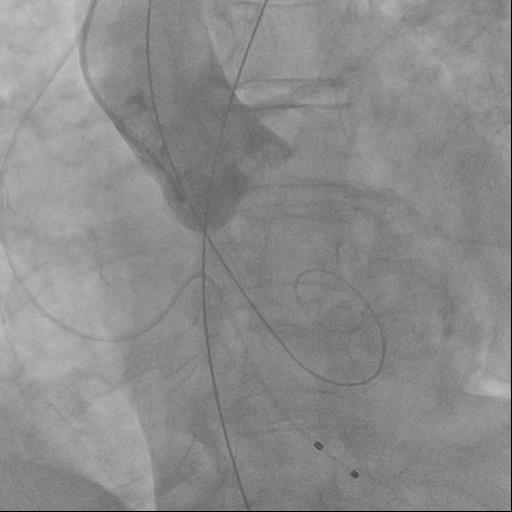

The rightsubclavian vein was punctured. A 6F intraducer was inserted. The endocardialelectrode for temporary cardiac stimulation was placed in the right ventricularcavity. The left radial artery was punctured. A 6F intraducer was placed, andan invasive pressure line was connected. The left common femoral artery waspunctured. The 6F intraducer is inserted. Pigtail 6 F diagnostic catheter isinserted into the non-coronary sinus. Puncture of the right common femoralartery was performed. Two intravascular sutures were placed using the Pro Glidepre-stitching technique. The 12F intraducer was placed in the lumen of the rightfemoral artery. The Confida wire wasguided into the left ventricular cavity. Aortic valve valvuloplasty wasperformed using balloon catheters 20.0-40.0 mm, 25.0-40.0 mm. Asystole wasregistered on ECG and resuscitative measures were started. During indirectheart massage, endovascular prosthesis Portico - 29mm was implanted in aorticposition. At the control aortography, the aortic valve prosthesis is optimallyspread out.